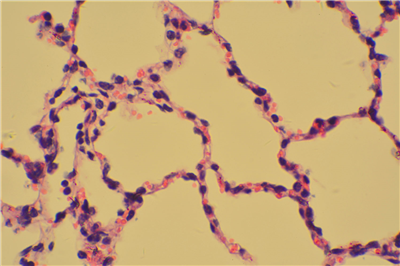

• HE染色

常规染色或HE(Haematoxylin and eosin)染色。它是病理技术中常用的一种方法,通过它可以做出病理诊断和发现寻求别的辅助方法,以达到准确,完整的病理诊断。苏木精染液为碱性 ,主要使细胞核内的染色质与胞质内的核糖体着紫蓝色 ;伊红为酸性染料 ,主要使细胞质和细胞外基质中的成分着红色 。HE染色法是组织学、胚胎学、病理学教学与科研中基本、使用广泛的技术方法。